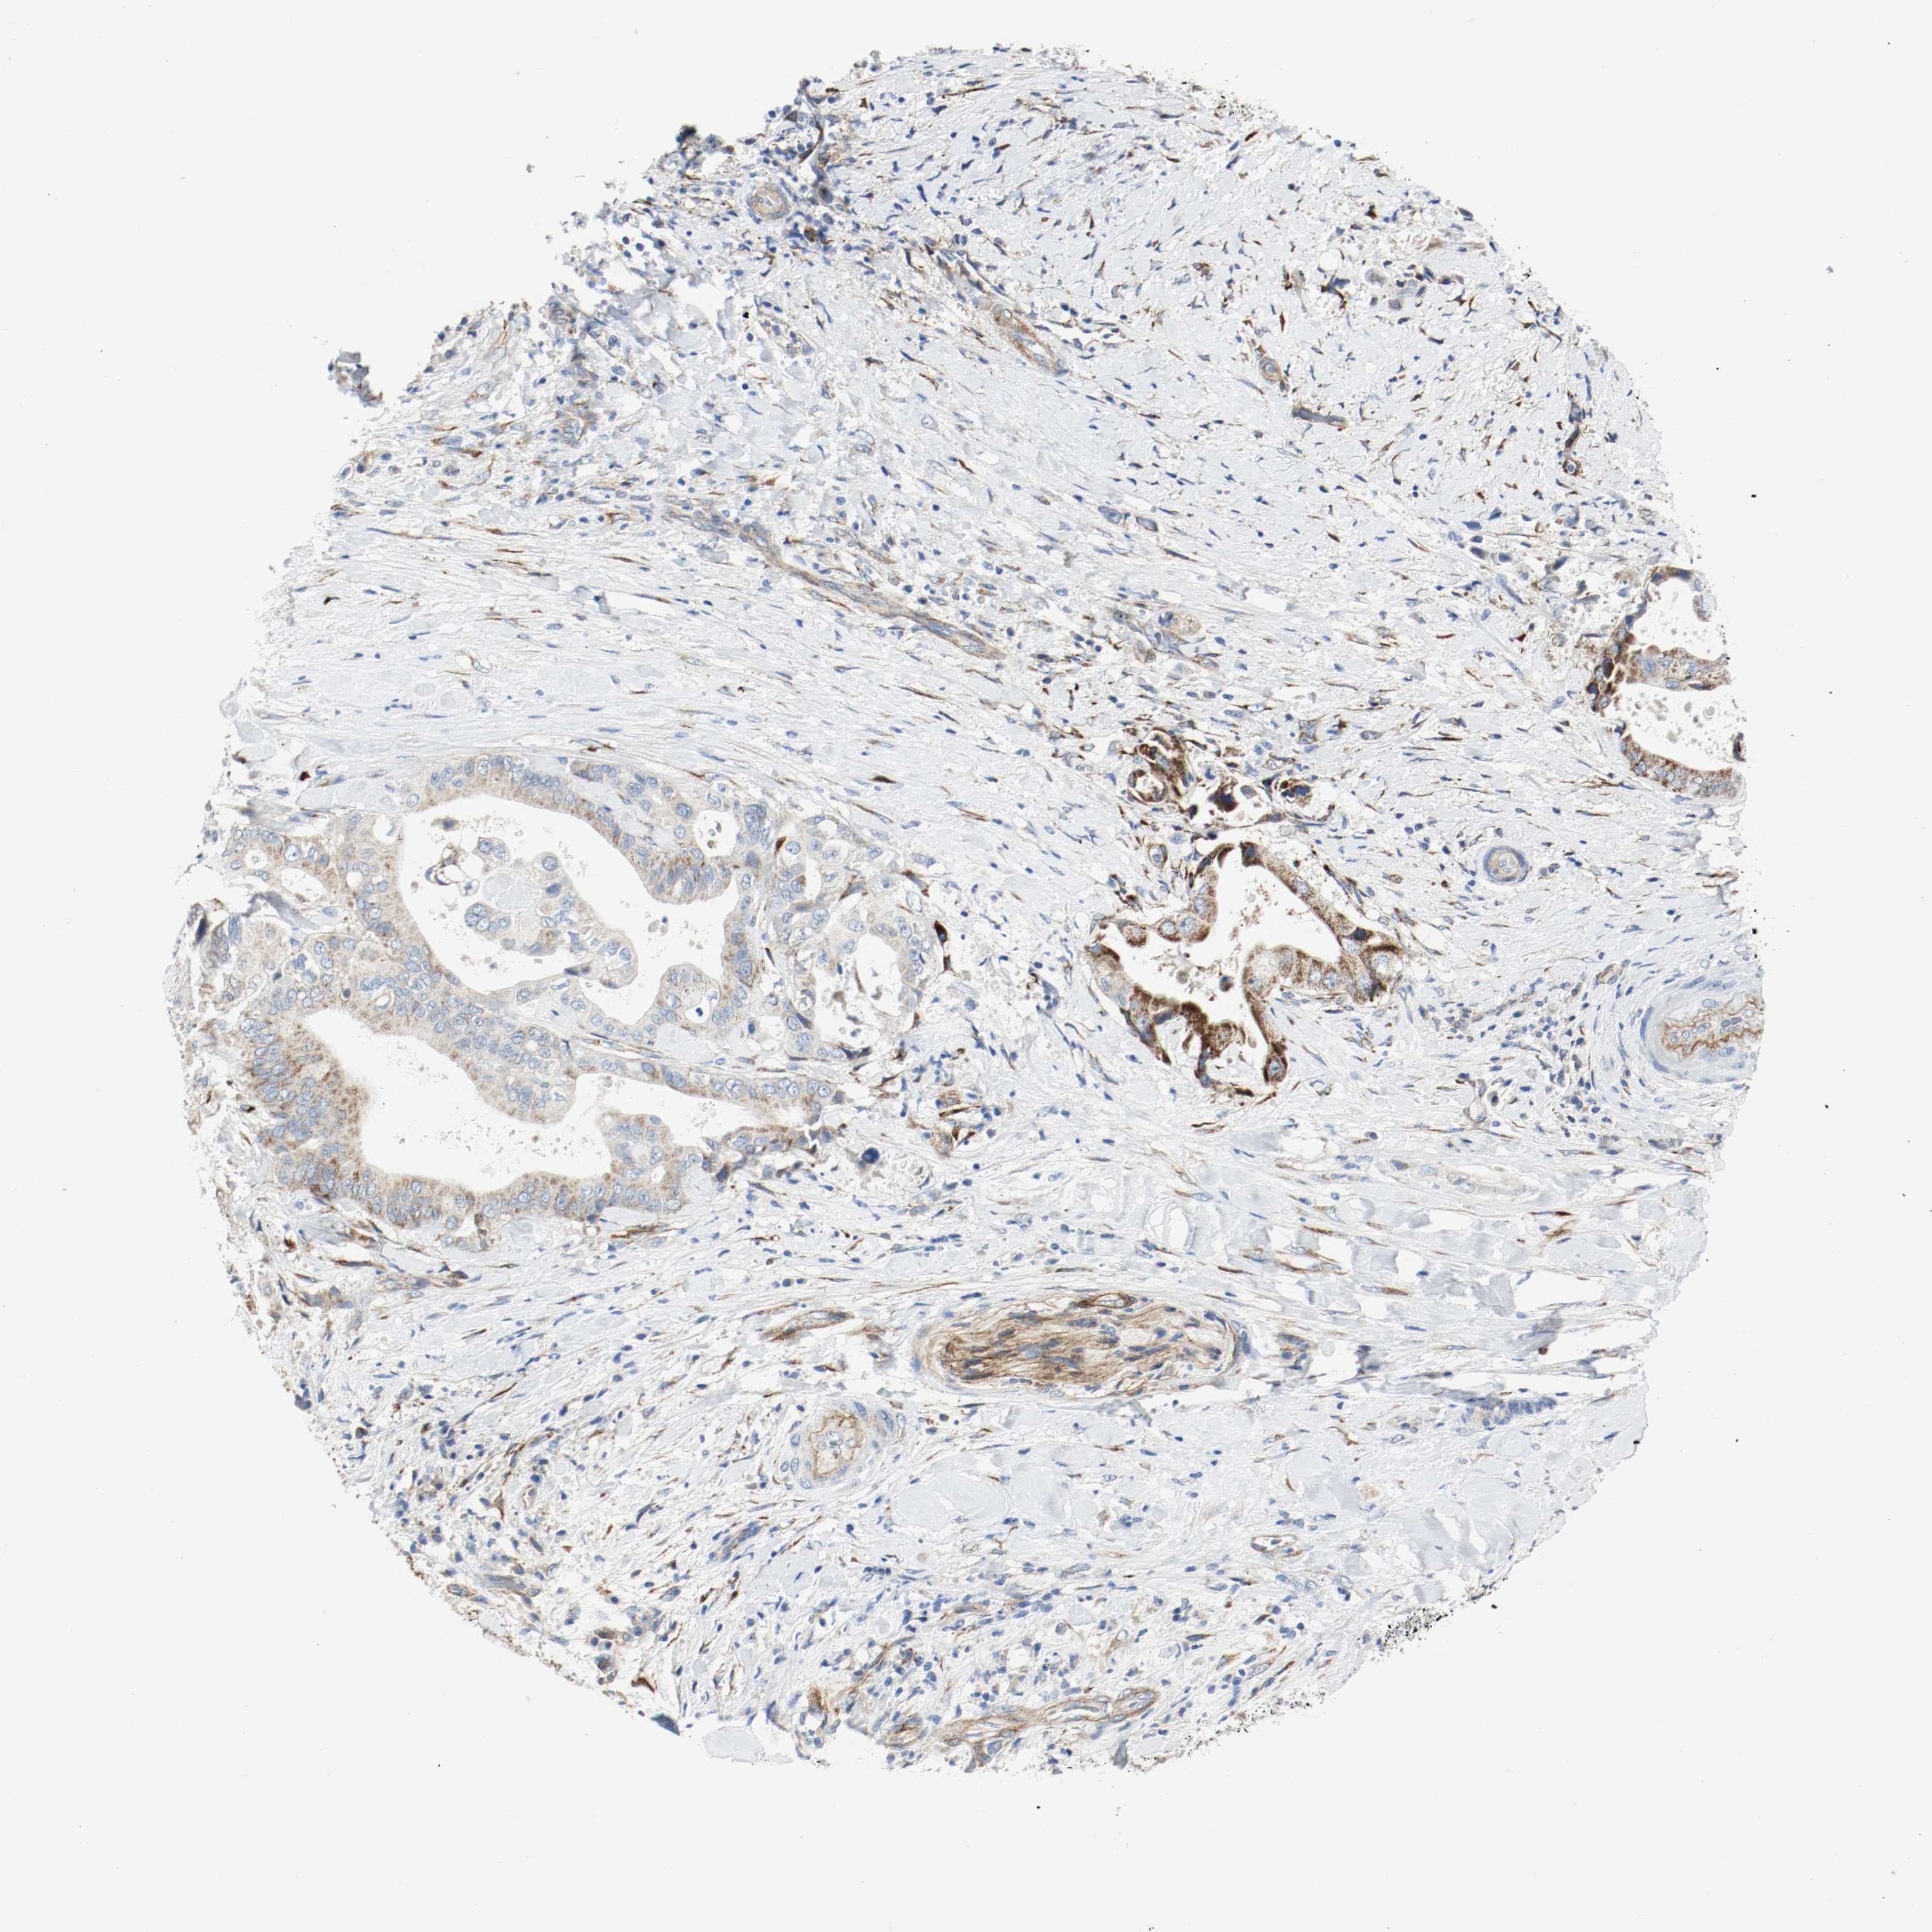

LIVER CANCER - Protein expressioni

A mouse-over function shows sample information and annotation data. Click on an image to view it in a full screen mode. Samples can be filtered based on level of antibody staining by selecting one or several of the following categories: high, medium, low and not detected. The assay and annotation is described here.

Note that samples used for immunohistochemistry by the Human Protein Atlas do not correspond to samples in the TCGA dataset.

Antibody stainingi

Antibody staining in the annotated cell types in the current human tissue is reported as not detected, low, medium, or high, based on conventional immunohistochemistry profiling in selected tissues. This score is based on the combination of the staining intensity and fraction of stained cells.

Each image is clickable and will lead to virtual microscopy that enables deeper exploration of all samples and also displays staining intensity scores, fraction scores and subcellular localization as well as patient and tissue information for each sample.

Antibody HPA004056

Antibody HPA004132

Antibody CAB004256

Staining

High

Medium

Low

Not detected

Intensity

Strong

Moderate

Weak

Negative

Quantity

>75%

75%-25%

<25%

None

Location

Nuclear

Cytoplasmic/membranous

Cytoplasmic/membranous,nuclear

Cholangiocarcinoma

Carcinoma, Hepatocellular, NOS